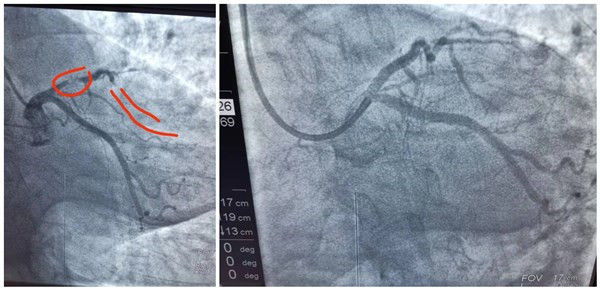

患者心肺复苏复苏成功后,由心内科急诊造影显示为冠状动脉左前降支原来放置支架处血栓形成阻塞,抽吸血栓并再植入支架1枚血管再通良好